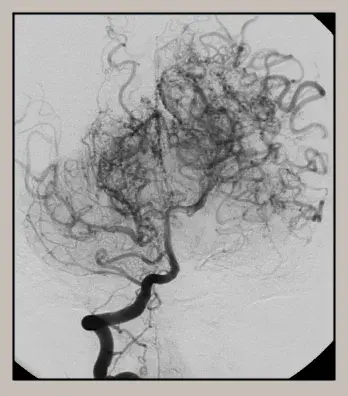

뇌의 바닥 쪽에 있는 뇌혈관 중 내경동맥의 끝부분과 그곳에 연결된 동맥 분지들이 이유 없이 안쪽부터 두꺼워져 막히고, 막힌 혈관을 대신하기 위해 가느다란 혈관들이 생겨나는 희귀병입니다.

가느다란 혈관은 막힌 동맥들이 혈액을 공급하던 곳에 대신 혈액을 공급해 주나 크기가 작기 때문에 다시 막히기도 쉬워 문제가 됩니다.

모야모야병은 선천성이나 후천성으로 경동맥 사이폰 부위에 양측성 폐색과 함께 뇌기저부에 동맥과 세동맥들이 미세한 측부로를 형성하기 때문에 연기가 피어오르는 듯한 특징적 소견을 나타냅니다.

모야모야병 진단은 CT, MRI, 혈관 조영술, MRI 혈관조영술, SPECT을 통해 이루어집니다. CT 촬영으로 모야모야병을 진단하기는 어렵지만 수술의 필요성, 수술 시기, 병의 진행 양상을 확인하기 위해 필요합니다.